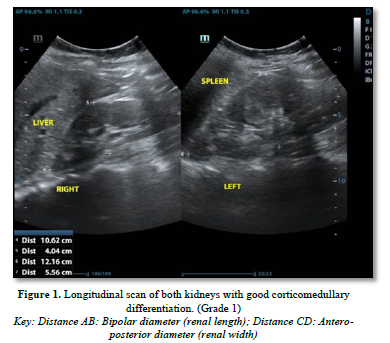

The following parameters were measured (Figures 1 & 2):

Renal length: Longitudinal bipolar maximum (pole to pole)-normal length: 9-12cm

Cortico-medullary differentiation was assessed as the visualization of the pyramid /cortex as distinct from the sinus and graded as maintained, poorly maintained, or lost.